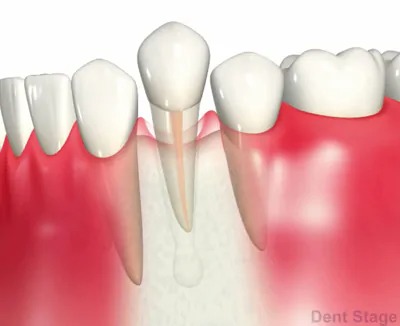

7根管充填

症状があれば日にちを空けて充填します。

ゴムの様な材質で緊密に詰めていき、再度細菌が繁殖しないようにスペースを閉鎖します。

最後にレントゲンで確認します。